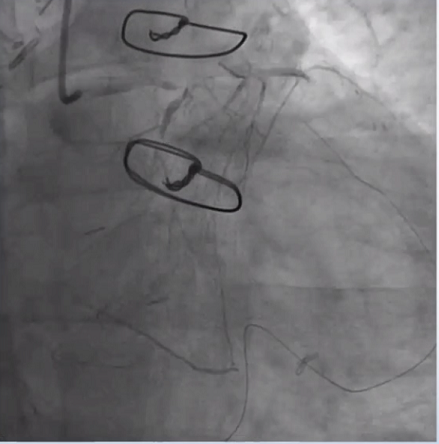

侧支循环穿孔可分为不同类型,如室间隔支穿孔、心外膜支穿孔。研究显示,侧支循环的类型与手术成功率相关,心外膜支穿孔则手术成功率较低,但侧支循环类型与主要不良心血管事件MACE的发生风险并无显著关联。(图1)

图1 侧支循环类型和手术成功率及MACE事件的关系